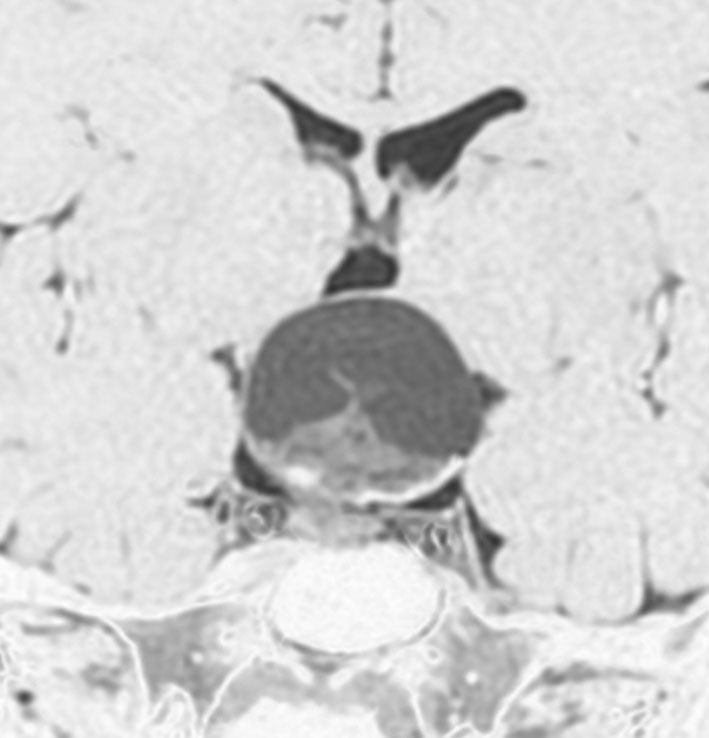

成人の第3脳室内部に局在する頭蓋咽頭腫です。経脳梁法で両側のモンロー孔から全摘出しました。下垂体組織は残っています。これは乳頭状頭蓋咽頭腫と呼ばれるもので,成人にしか発生しません,のう胞がなく石灰化もないのが大きな特徴です。境界が明瞭で柔らかく摘出が簡単なタイプとして知られています。この患者さんも術後に下垂体機能不全も視床下部障害も生じませんでした。